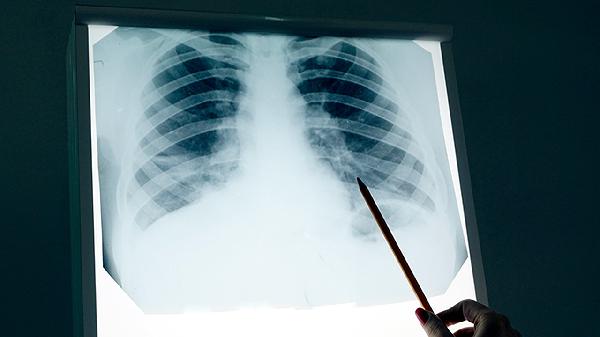

幽門管癌的癥狀可能與其他胃部疾病相似,因此出現(xiàn)上述癥狀時(shí)應(yīng)及時(shí)就醫(yī)檢查。建議保持規(guī)律飲食,避免辛辣刺激性食物,戒煙限酒。確診后應(yīng)積極配合醫(yī)生治療,治療方案可能包括手術(shù)、化療、放療等綜合治療手段。定期胃鏡檢查有助于早期發(fā)現(xiàn)胃部病變,特別是對于有胃癌家族史或長期胃部不適的人群更為重要。